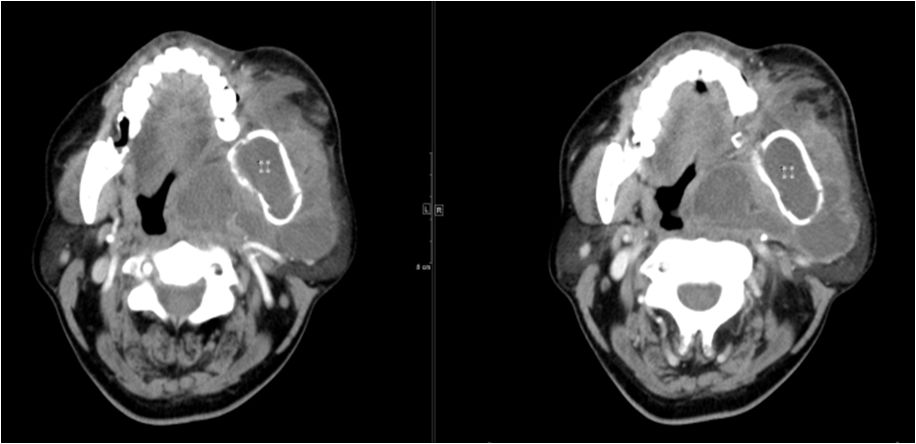

04 咀嚼肌间隙、颌下间隙、左侧颞下间隙,颊间隙,翼颌间隙

男,55岁,左下后牙反复肿疼1年余,加重1月余,疼痛剧烈伴张口受限,面部肿胀。

咀嚼肌间隙有脓肿形成。